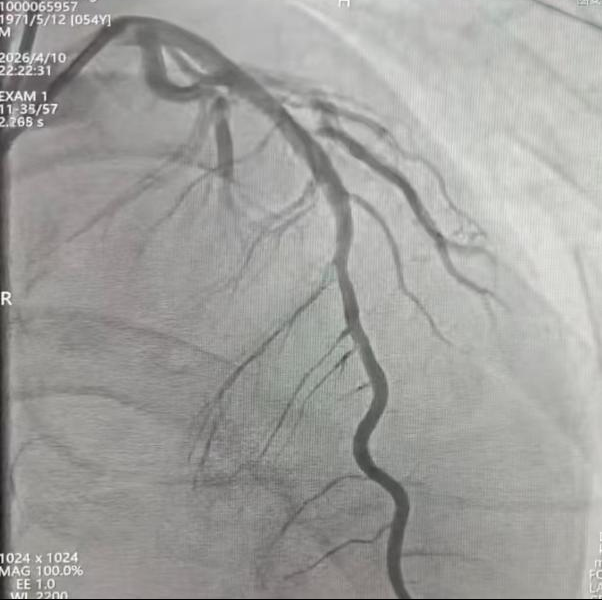

术中造影清晰地揭示了病变本质:前降支(LAD)近、中段100%闭塞——这是导致广泛前壁心梗、心源性休克、心脏骤停的“罪魁祸首”。其他血管也存在不同程度的狭窄。

李超民主任团队精准操作:导丝通过闭塞段,球囊预扩张,随后精确植入一枚药物洗脱支架。术后造影显示:前降支血管狭窄完全消失,血流通畅。他们用极短的时间,重新打开了患者生命的“主干道”。

介入治疗后冠脉造影